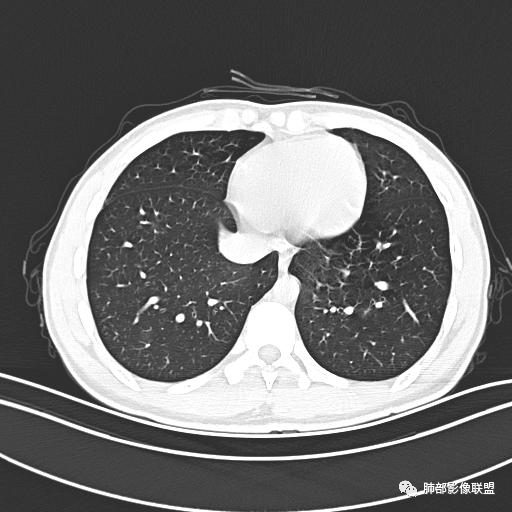

小强:青年,发热,皮疹;双肺散在结节,周围磨玻璃,点晕征,疱疹病毒感染,鉴别荚膜组织胞浆菌,结核。 大雄:青年,急性起病,发热伴全身皮疹2天,抗病毒治疗体温有下降。双肺随机分布大小不等类圆结节,“点晕征”。考虑水痘-疱疹病毒(VZV)血播询问接触史,查体皮疹分布以及形态基本可诊断。 王开金江津中心医院呼吸科:青年男性,起病急,病程短,以发热,皮疹为首发症状,感染指标以单核细胞升高为主,胸部ct双肺多发结界,周围有晕,点晕表现,随机分布,同意於老师意见,水痘疱疹病毒血流感染累及肺。 王秀仙:双肺多发大小不等结节,周围有晕,边缘模糊,呈点晕征表现。青年,急性起病,发热伴全身皮疹2天,抗病毒治疗体温有下降。考虑疱疹病毒。鉴别荚膜组织胞浆菌。 傅昌瑜:19岁男性,发热、全身皮疹2天,单核细胞增高,双肺多发结节,结节边缘见边界不清磨玻璃影。点晕征+发热、全身皮疹+单核细胞增高——考虑水痘-带状疱疹病毒肺炎。 一切∮随缘:年轻男性,发热,皮疹两天,实验室,CRP,PCT增高,影像:双肺多发散在磨玻璃结节,边界欠清,大小不等,呈点晕征改变,以血管束周围分布为主,局部血管束略增粗,其它无明显改变,考虑:1:病毒性肺炎(水痘疱疹病毒?不知道皮肤有无改变)2:真菌(组织胞浆菌,血管侵袭性肺曲霉)3:GPA4:寄生虫(实验室没有看到嗜酸细胞增高) 赵山河:双肺散在结节,周围有晕,边缘模糊,呈点晕征表现。青年,急性起病,发热伴全身皮疹2天,抗病毒治疗体温有下降。考虑水痘—疱疹病毒感染。洪桥爱:青年男性,发热、皮疹2天,伴瘙痒,皮疹于面部首发,之后进展至全身,虽然没有对皮疹进行描述,但是从出疹时间及皮疹进展情况,伴瘙痒,应该就是个水痘患者;CT提示双肺随机分布结节影,部分结节伴有边界不清晕征,考虑水痘血播肺。 刘强:年轻男性,急性起病,皮疹,发热,抗感染治疗体温下降,说明有效。影像表现为散在点晕征,感染类疾病谱(疱疹病毒,真菌,结核),结合年龄,皮肤皮疹,考虑水痘-疱疹病毒性肺炎。 小兜:男性,19岁,发热皮疹两天,颜面部至全身,CRP,降钙素及单核增高。CT示双肺散在小结节,周围伴磨玻璃影,点晕征,考虑为水痘-带状疱疹病毒(varicella-zoster virus,VZV)肺炎 必有路:青年,皮疹+发热+“点晕征”→水痘-疱疹病毒(VZV) 许慧良:青年男性患者,发热、皮疹2天,体温最高38.5℃,第3天皮疹扩展至全身,伴瘙痒,胸部CT:双肺多发随机分布的小结节,结节周边见边界模糊的晕征,考虑水痘病毒感染流心明智:男,19,急性起病,发热伴全身皮疹2天。出疹顺序头→全身,抗病毒有效。胸部CT:两肺多发大小不等类圆形实性小结节影,随机分布,结节周围环绕GGO,边界模糊,呈点晕征。出疹特点是关键,未提示。考虑:血播病毒性肺炎,水痘-疱疹病毒?麻疹?鉴别荚膜组织胞浆菌、TB、血管炎、寄生虫等。 浪迹天涯:病灶多为5-10mm大小结节,结节周围可见磨玻璃样的晕环,常多发,可分布于肺内任何区域,考虑水痘—带状疱疹病肺炎如果短时间内有新的一个区域浸润,更加能说明,